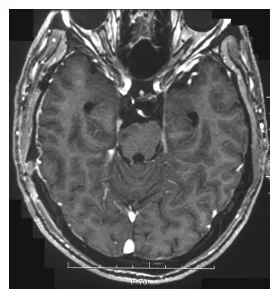

病理检查显示典型施万细胞瘤栅栏样结构,伴多处出血区及薄壁扩张血管。患者术后恢复顺利,偏瘫改善,1周后出院。术后4个月MRI未见肿瘤复发(图3)。

图3.术后MRI显示肿瘤大体全切,脑干受压解除。